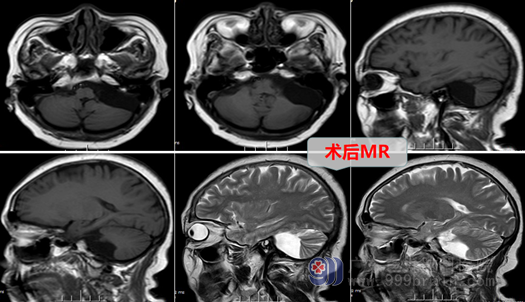

7月3日,外十科团队为杨阿姨进行手术:全麻下左侧桥小脑角区蛛网膜囊肿部分囊壁切除+脑池打通术,术中在高清显微镜下切除大部分囊肿壁,暴露并保护好三叉神经、面听神经、外展神经、后组颅神经等,部分囊壁与颅底硬膜相粘连,予以分离切除,并予以打通桥前池,环池;手术过程顺利,正常结构保护完好,术后杨阿姨头晕、眩晕等症状解除了,她恢复良好,无任何后遗症,杨阿姨又可以享受美好人生了。